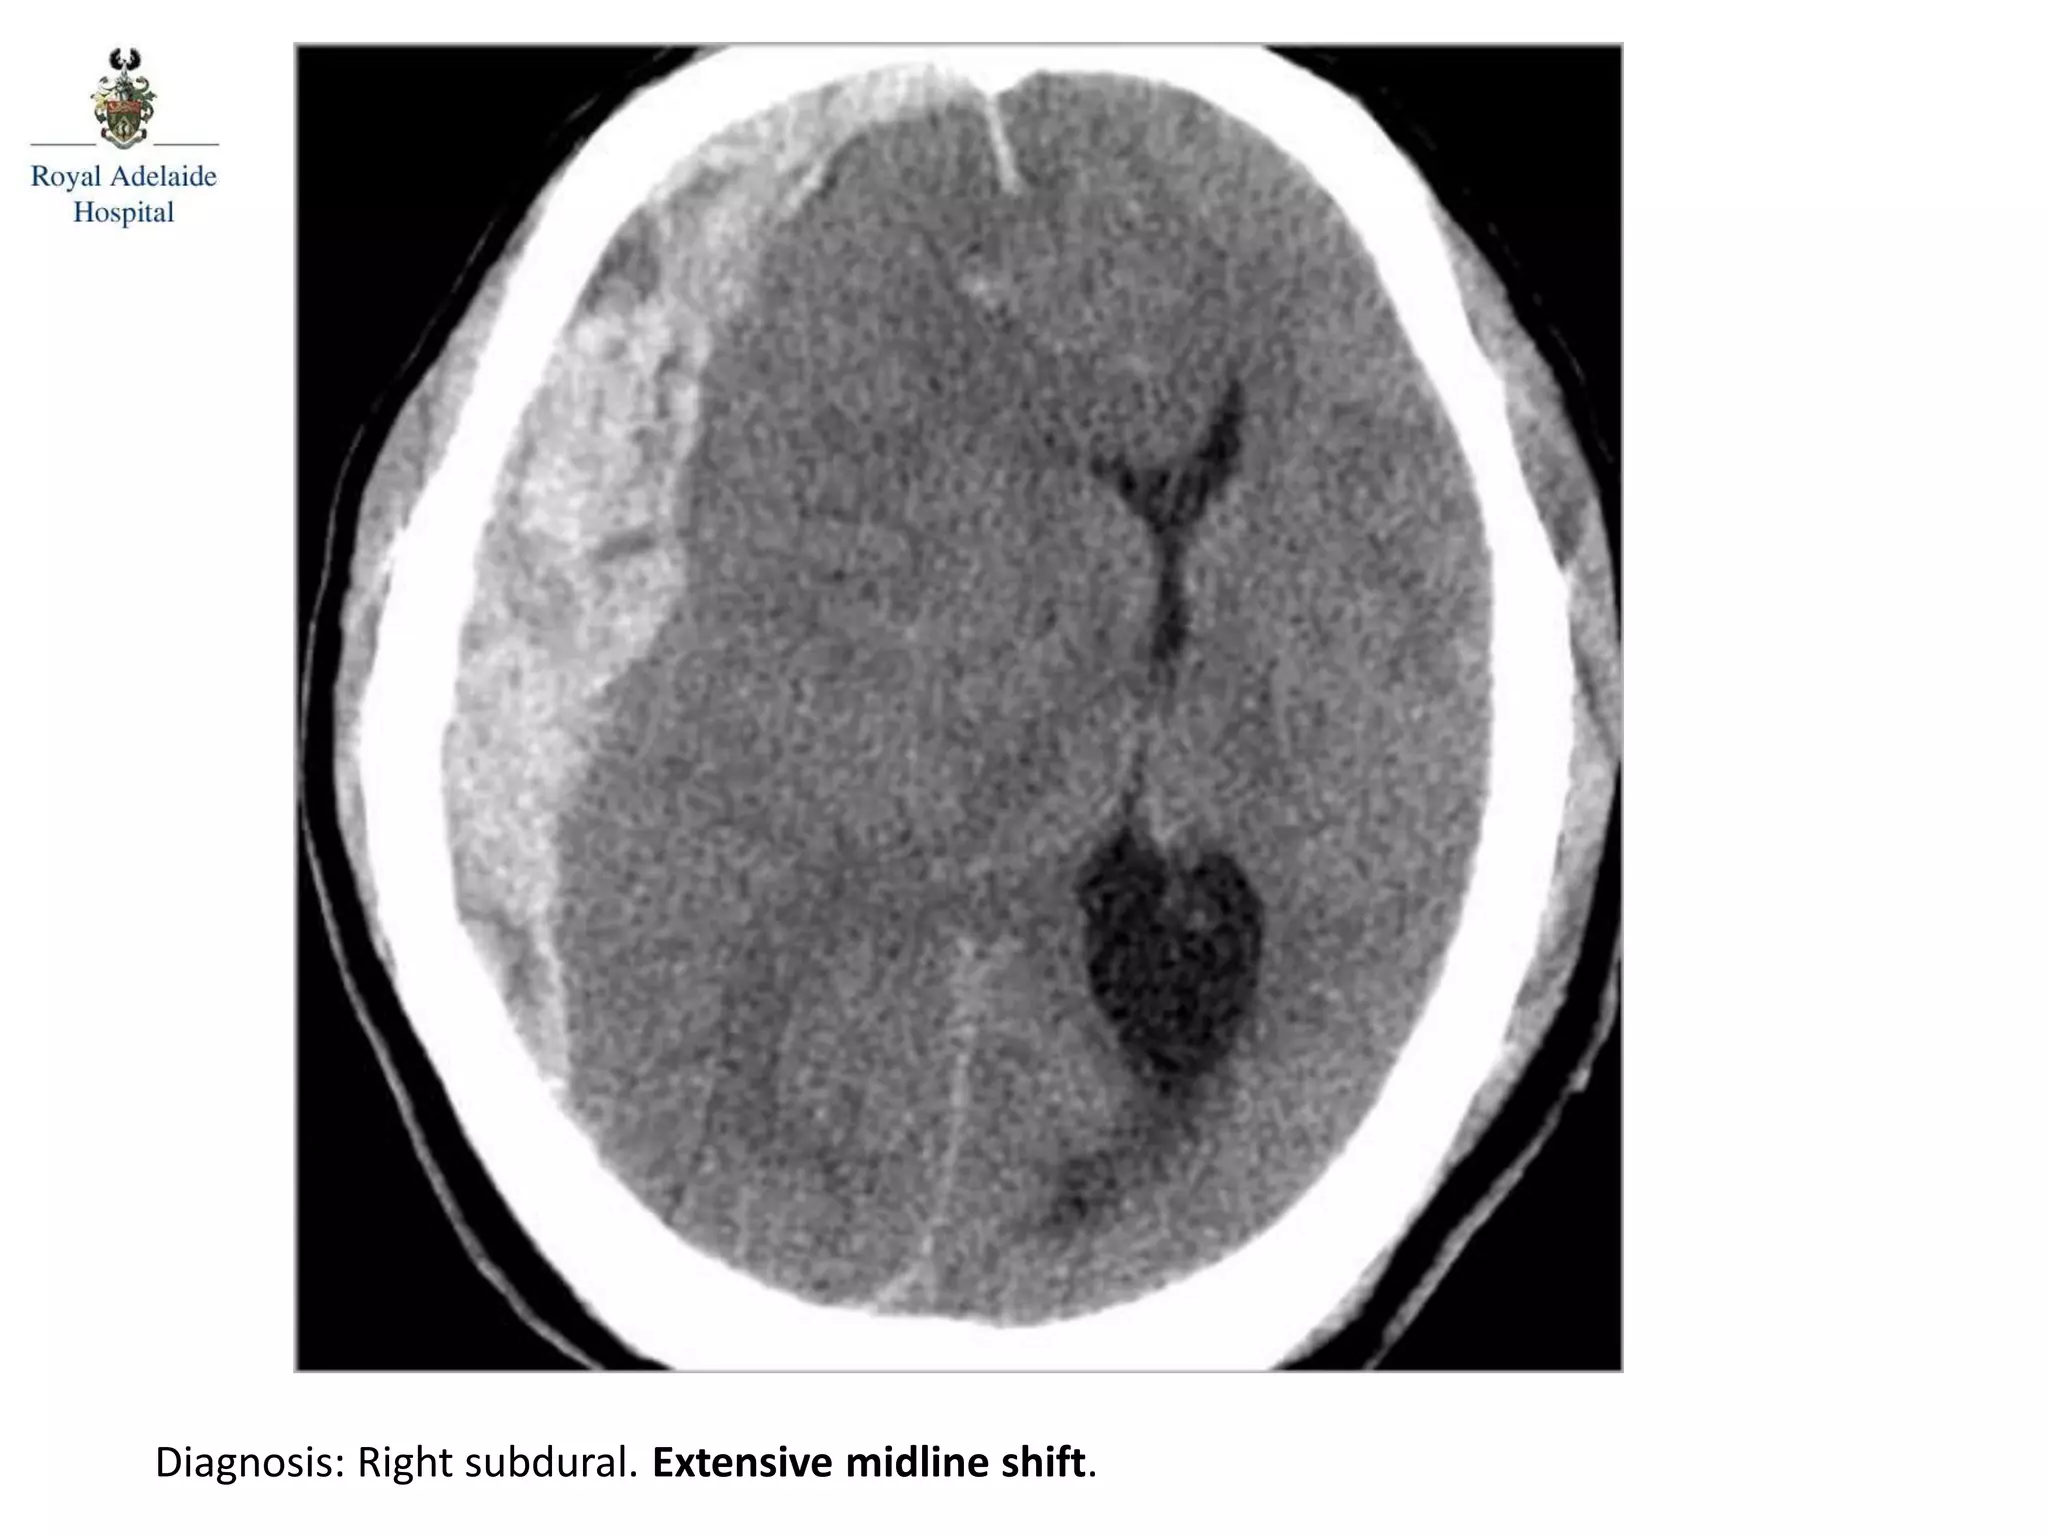

The document outlines multiple diagnoses from head CT cases, including small left basal ganglia bleed likely due to hypertension, various types of subdural and subarachnoid hemorrhages, and evidence of hydrocephalus. It details traumatic origins of some hemorrhages and notes obstructing masses and atrophic changes. Overall, there are significant findings indicating complications related to cerebral hemorrhages and ventricular enlargement.